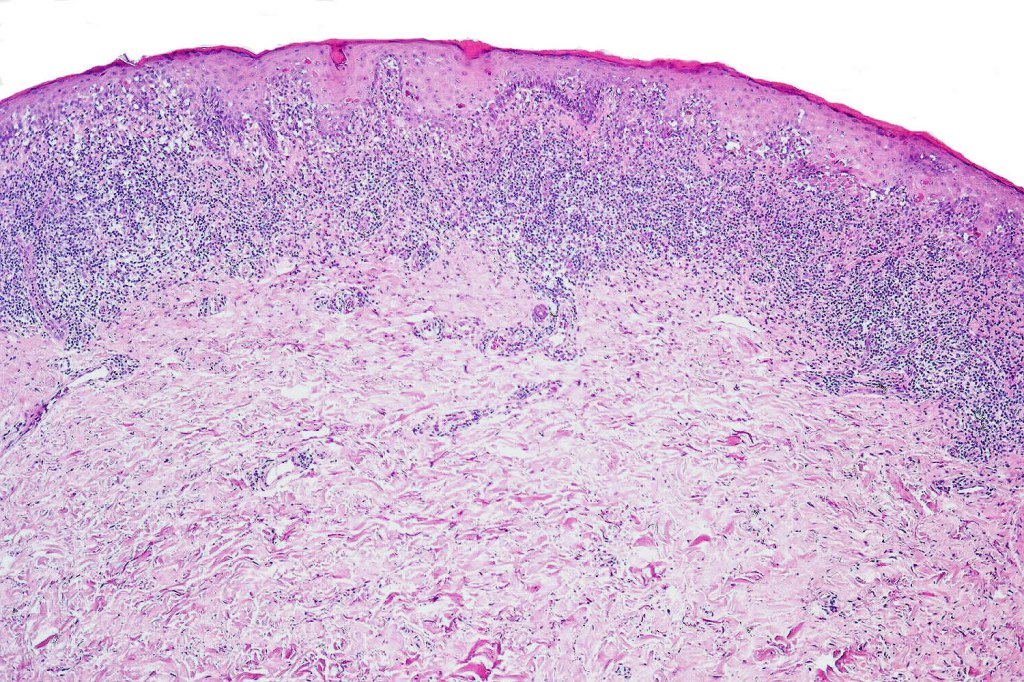

Histological features

•Hyperkeratosis +/- parakeratosis

•Wedge-shaped hypergranulosis

•Generally irregular (sometimes saw-tooth) acanthosis but may show broad acanthosis

•Interface change

•Conspicuous cytoid bodies

•Pigment incontinence

•Band-like or perivascular infiltrate of lymphocytes, histiocytes with occasional eosinophils & plasma cells

. Late lesions are charcterized by epidermal atrophy, papillary dermal fibrosis, pigment incontinence & a perivascular or interstitial lymphocytic infiltrate